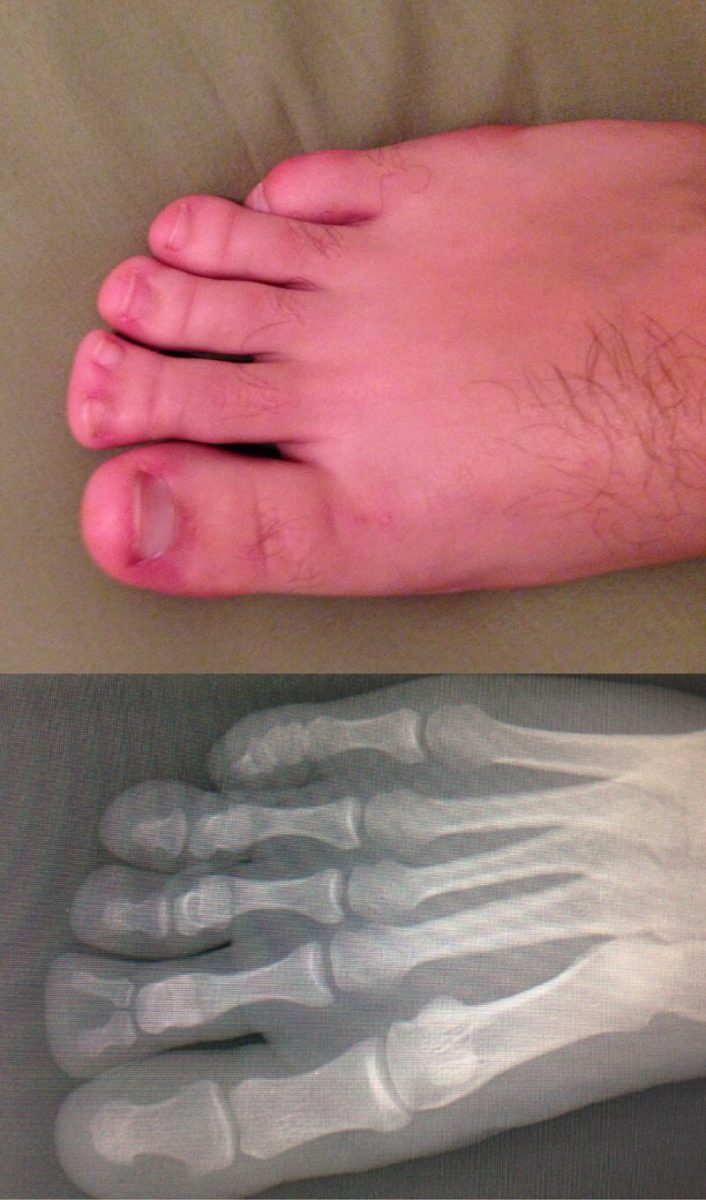

Пациент выслал фото врачу. Тот долго не мог понять, что со стопой. Просто выбирайте нормальный фон!